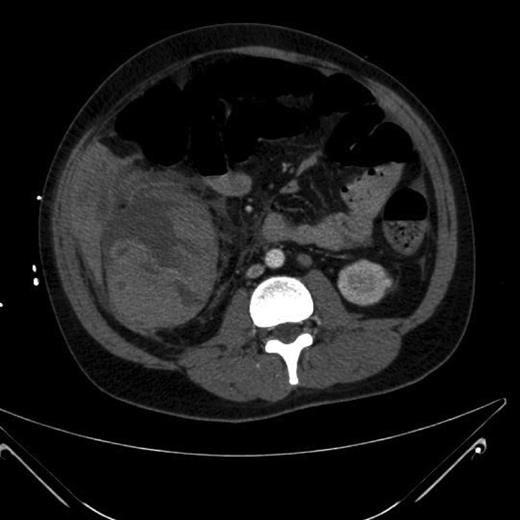

Seventy-two hours after starting his anti-tubercular therapy, he took a turn for the worse and was transferred to the ICU for ventilatory and inotropic support. He had ∼1 l of bleeding per rectum and dropped his haemoglobin (Hb) from 140 to 65 g/l. An oesophagogastroduodenoscopy showed no cause for upper GI bleeding. A CT abdomen + pelvis with contrast was performed, which showed a large (20 cm) inflammatory caecal mass with a moderate amount of intra-abdominal free fluid (Fig. 2). Selective angiography of the superior mesenteric artery demonstrated the bleeding point in the caecum and this was embolized superselectively with coils (Fig. 3).

CT abdomen + pelvis with contrast: large inflammatory caecal mass.